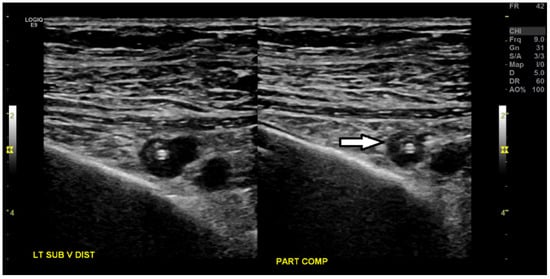

3. Case Presentation